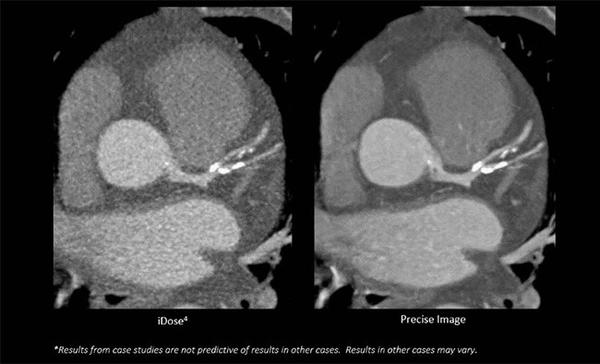

AI技術を応用した「Precise Cardiac」を開発することで,心臓検査でしばしば発生する画像のブレを自動的に抑え,心臓CTの画質向上に大きく貢献する。またAI技術の「Precise Image」を使用することで,心臓CTの根本的な画質を向上させながら,同時に大幅な被ばく低減を実現する。80%の被ばく低減をした場合,85%のノイズ低減と60%の低コントラスト検出能の向上が可能となった[4]。

「Precise Image」使用前(左),使用後(右)